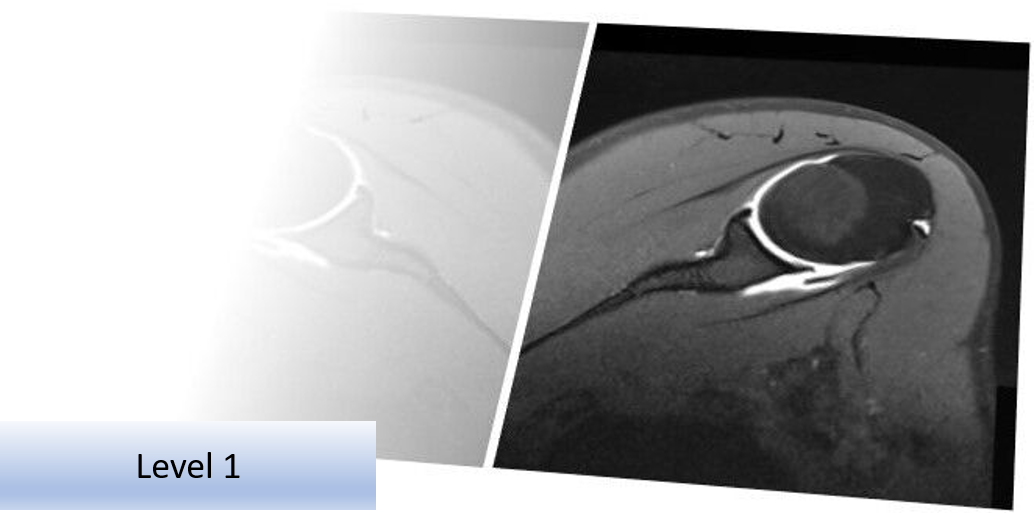

MSK Imaging Referral and Interpretation Course (Online) 2x half day - Level 1

To include fundamentals of safe and appropriate referring for medical imaging tests, imaging management of various conditions, normal cross sectional imaging anatomy and pathology, image reporting and acting on the imaging results.

This interactive 2 x half day online course will provide you with the skills and information to make the most clinically appropriate and cost effective use of diagnostic imaging for your patient and improve your image interpretation skills and understanding of the radiology report. MRI, Ultrasound and X-ray imaging are increasingly used to provide additional information which may reinforce or change patient management.

Included are topics on safe and appropriate referring, imaging management of MSK conditions, normal cross sectional imaging anatomy and pathology, image reporting and acting on the imaging results.